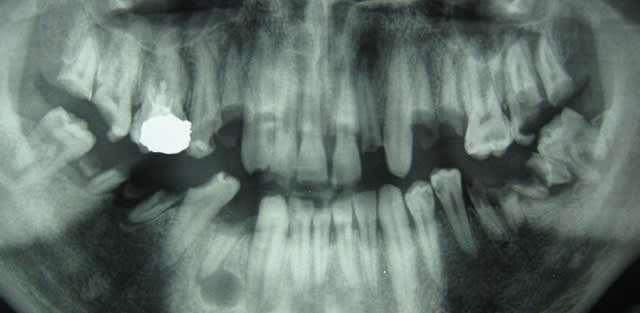

voici un jeune patient vu en urgence, le radiologue du coin fait la pano ds l'urgence aussi

antibio avant de preparer les alvulsions.....

jamais revenu

le france est un pays developpé ou il a tjrs vecu (vive le fluor!!)

même le traitement radiculaire sur 16 est abimé pffff!